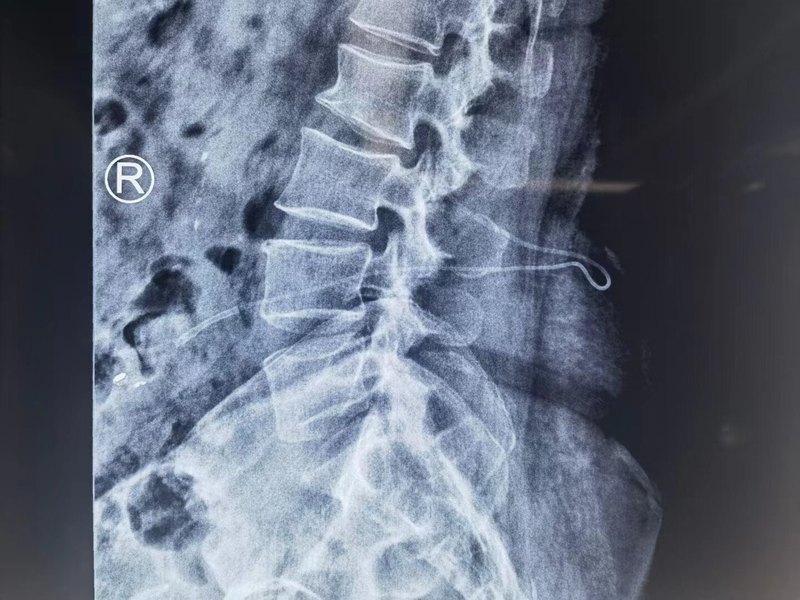

患者女,29歲,安徽無為市人。一、李小勇腦脊液科入院前病史患者于2005年7月初,出現(xiàn)頭暈,步態(tài)不穩(wěn),記憶力減退;一周后癥狀未見自行改善,就診于江蘇省江陰某醫(yī)院,醫(yī)生認(rèn)為跟腰椎有關(guān),但查腰椎影像(圖-1)后未見異常。圖-1:2005年7月18日腰椎影像但1年時間內(nèi),仍時有頭暈,步態(tài)不穩(wěn),記憶力減退的癥狀,但能自行好轉(zhuǎn),所以患者未太在意,但1年后增加了頭痛,惡心癥狀加重的情況,于是2006年8月9日,第2次就診于江蘇省江陰市某醫(yī)院,查頭顱核磁示腦積水(圖-2)。圖-2:2006年8月9日頭顱增強(qiáng)核磁為治療腦積水,于6天后即2006年8月15日就診于上海的某三甲醫(yī)院,入院時查頭顱核磁示腦積水(圖-3)。圖-3:2006年8月15日頭顱核磁入院后完善各項(xiàng)檢查后于2006年8月23日,進(jìn)行了腦室腹腔分流術(shù)(圖-4)。術(shù)后癥狀消失,住院半月左右出院。圖-4:2006年8月23日頭顱CT第1次腦室腹腔分流術(shù)后8個月即2007年5月1日,再次出現(xiàn)頭暈頭痛,在江蘇省江陰市某醫(yī)院查頭顱CT(圖-5)后傳給給予手術(shù)醫(yī)生,醫(yī)生考慮是分流管堵塞。圖-5:2007年5月1日頭顱CT因分流管堵塞,2007年5月2日(第1次腦室腹腔分流術(shù)后8個月),第2次住入給予手術(shù)的醫(yī)院,2007年5月5日(入院后3天),術(shù)后例行查頭顱CT(圖-6)后,加做了腦室腹腔分流術(shù),但保留了原腦室分流管。圖-6:2007年5月5日頭顱CT第2次腦室腹腔分流術(shù)后次日,查頭顱CT示腦室縮小,腦室內(nèi)有兩根管(圖-7)。術(shù)后半月余癥狀慢慢消失,之后出院。圖-7:2007年5月6日頭顱CT上海第2次腦室腹腔分流術(shù)后3月余即2007年8月15日,查頭顱CT示未見異常(圖-8)。圖-8:2007年8月15日頭顱CT2019年12月13日(第2次出院后12年),因再次出現(xiàn)記憶力減退,走路不穩(wěn),嘔吐,視物模糊,復(fù)視的癥狀第3次就診給予手術(shù)的醫(yī)院。于入院后2019年12月30日,進(jìn)行了第3次進(jìn)行了腦室腹腔分流術(shù)(分流閥初始壓力2.0),仍保留了原2根腦室分流管;術(shù)后當(dāng)天查頭顱CT示腦室仍有擴(kuò)張,腦室內(nèi)有3根管(圖-9)。圖-9:2019年12月30日頭顱CT第3次腦室腹腔分流術(shù)后1個月即2020年2月初,再次出現(xiàn)記憶力減退視物模糊,再過1個月仍無任何改善,于2020年3月17日(第3次腦室腹腔分流術(shù)后2個半月),到江蘇省江陰某醫(yī)院檢查了頭顱CT示腦室仍擴(kuò)張(圖-10)。圖-10:2020年3月17日頭顱CT查頭顱CT后次日即2020年3月18日,第4次就診給予手術(shù)的醫(yī)院,將分流閥壓力調(diào)為1.5,但調(diào)完壓回家后癥狀仍未明顯緩解。2020年4月5日(第1次調(diào)壓后18天),因癥狀持續(xù)不見減輕,到江蘇省江陰某醫(yī)院查頭顱CT示腦室仍擴(kuò)張(圖-11)。圖-11:2020年4月5日頭顱CT第3次腦室腹腔分流術(shù)后3月余即2020年4月7日(第1次調(diào)壓后20天),第5次就診于給予手術(shù)的醫(yī)院,第2次調(diào)分流閥壓為1,并遵醫(yī)囑回家后每日按壓儲液囊200次左右,癥狀稍有緩解。但第2次調(diào)壓僅2天后,癥狀又加重,到江蘇省江陰某醫(yī)院查頭顱CT示腦室仍擴(kuò)張(圖-12)。為求進(jìn)一步有效治療,通過網(wǎng)絡(luò)找到北京的李小勇腦脊液科。圖-12:2020年4月9日頭顱CT二、在李小勇腦脊液科治療過程和結(jié)果腦積水第1次腦室腹腔分流術(shù)后14年,即第2次腦室腹腔分流術(shù)后13年,即第3次腦室腹腔分流術(shù)后3個月半,5次就診于給予手術(shù)的醫(yī)院但仍腦積水,顱內(nèi)感染情況下于2020年4月11日,住入李小勇腦脊液科,入院時:頭暈伴視物不清,嘔吐,睡眠差,頭部有手術(shù)瘢痕(圖-13);入院時頭顱CT示腦積水,腦室內(nèi)有3根管(圖-14)。圖-13:2020年4月11日入院時圖-14:2020年4月11日入院時頭顱CT入院后4天即2020年4月15日,拔除了原3根分流管+兩側(cè)腦室外引流術(shù)(圖-15)。圖-15:2020年4月15日頭顱CT術(shù)后次日即2020年4月16日,查頭顱CT示腦室有縮小,有出血(圖-16),兩側(cè)腦室引流出血色腦脊液(圖-17)。圖-16:2020年4月16日頭顱CT圖-17:2020年4月16日入院治療8天即2020年4月19日,引流出的腦脊液血色變淡(圖-18);頭顱CT示出血變少(圖-19)。圖-18:2020年4月19日圖-19:2020年4月19日頭顱CT入院治療11天即2020年4月22日,查頭顱CT示腦室縮小,出血消失(圖-20),頭暈嘔吐消失。圖-20:2020年4月22日頭顱CT入院治療18天即2020年4月29日,進(jìn)行了腦室腹壁外引流術(shù),頭顱CT示腦室縮小,腦室內(nèi)僅有1根管(圖-21)。圖-21:2020年4月29日頭顱CT進(jìn)行治療3個月即2020年7月17日,腦積水已變完全清亮,且腦脊液化驗(yàn)各項(xiàng)指標(biāo)正常,擇期進(jìn)行腦室腹腔分流術(shù)。圖-22:2020年7月17日入院治療100天即2020年7月20日,進(jìn)行了腦室腹腔分流術(shù)。術(shù)后當(dāng)天查頭顱CT示腦室分流術(shù)后狀態(tài)(圖-23)。圖-23:2020年7月20日頭顱CT入院治療109天即2020年7月29日康復(fù)出院,出院時:頭暈嘔吐已完全消失2月余,視物不清也變正常,睡眠也變好(圖-24);出院時頭顱CT示無異常(圖-25)。圖-24:2020年7月29日圖-25:出院時頭顱CT